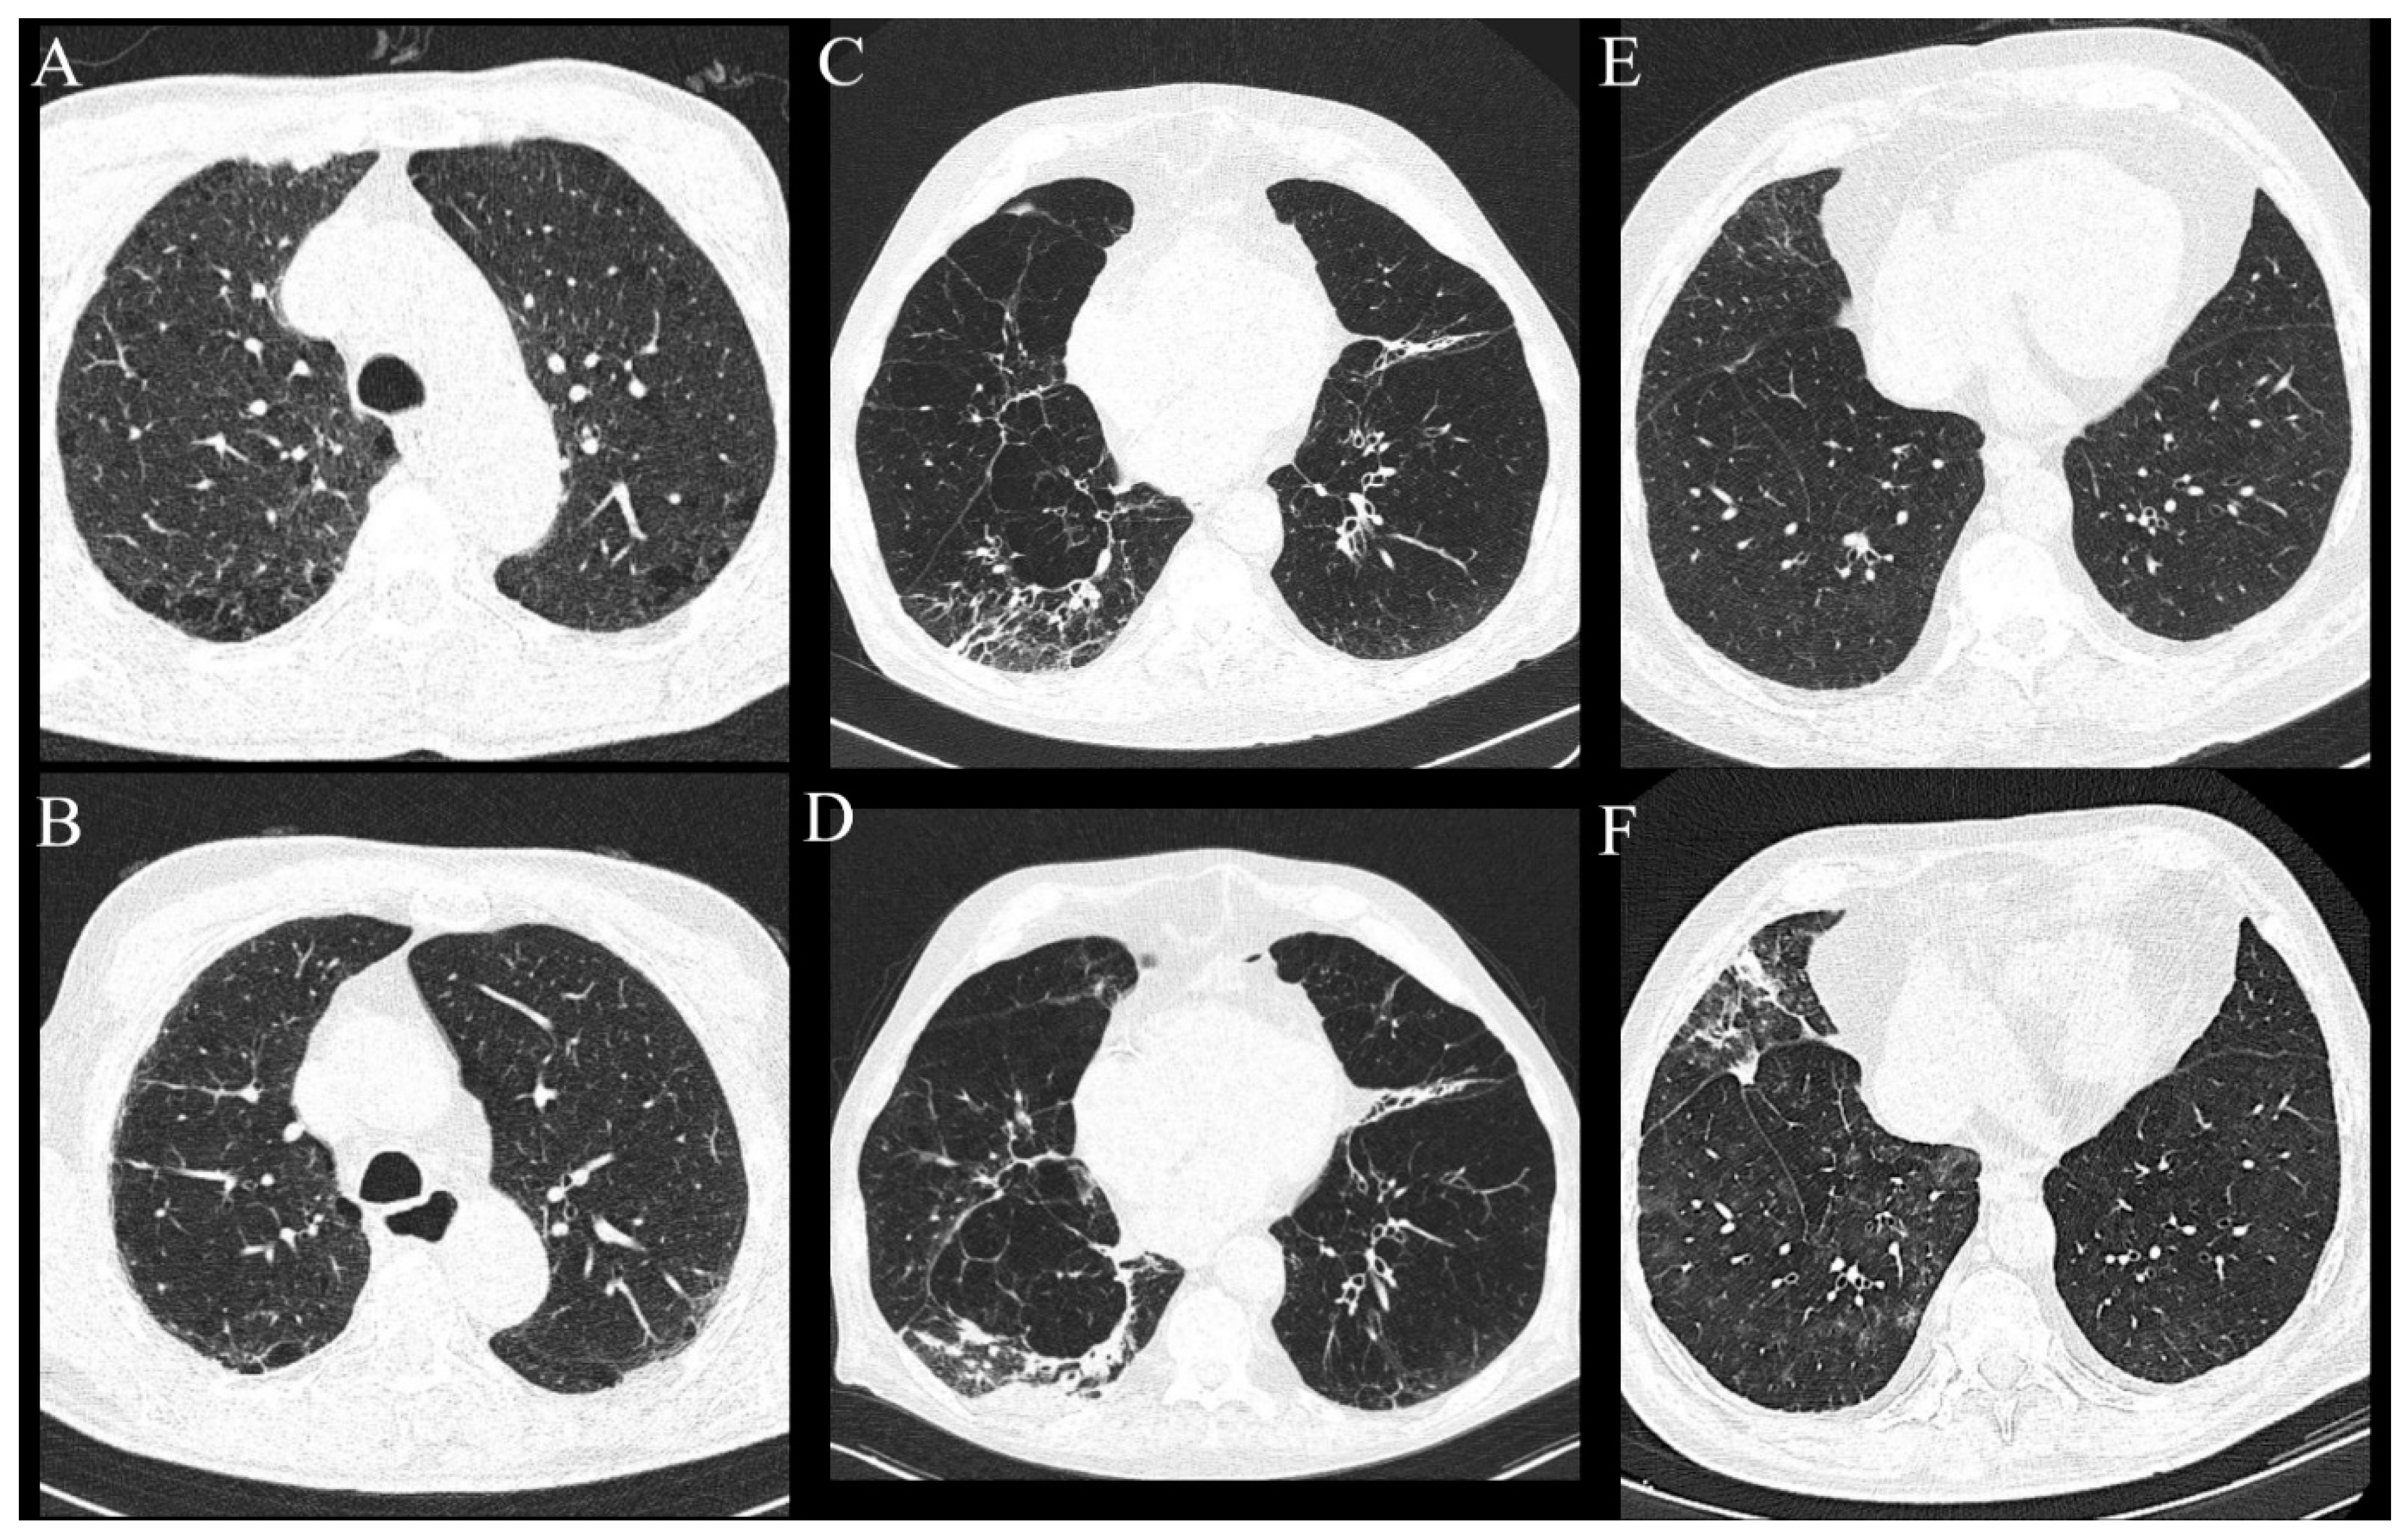

The follow-up lung MSCT scans were available for 65 out of 113 patients, of which 11 were patients with ILAs (11 of a total number of 15 with ILAs), within a median of 24 months (Q1-Q3 13–32 months) from the baseline lung MSCT performed. Progression of existing ILA changes was described in three patients (27.27%). The first patient, after having surgical resection and adjuvant chemoradiotherapy, developed new non-emphysematous cysts and more prominent subpleural reticulations in all lung zones with areas of GGO and was characterized as a possible usual interstitial pneumonia (UIP) pattern. The second and third patients, after having surgical resection followed by adjuvant radiotherapy, developed fibrous consolidations with GGO areas and newly developed reticulations (Figure 5). All patients had subpleural ILAs in the lower lung zones.

Figure 5.

Axial MSCT scans of lung parenchyma demonstrating progression of existing and newly developed findings in HNSCC patients after cancer treatment. (A,B) Patient had subpleural non-fibrotic ILA subcategory in the lower lung zones, but middle lung zones were not involved (as shown on the picture), and only paraseptal emphysema was visible. In the follow-up period, the patient demonstrated newly developed subpleural reticulations with zones of GGO, which was characterized as probable UIP pattern. (C,D) Same patient with progression of subpleural fibrotic ILAs manifested as fibrous consolidations in the right lower lobe and newly developed subpleural reticulations which persisted on subsequent scans. (E,F) Patient with progression of subpleural non-fibrotic ILA now seen as fibrotic consolidations, reticulations and areas of GGO. Patient had centrilobular nodules diffusely arranged throughout lung parenchyma, which became more prominent.